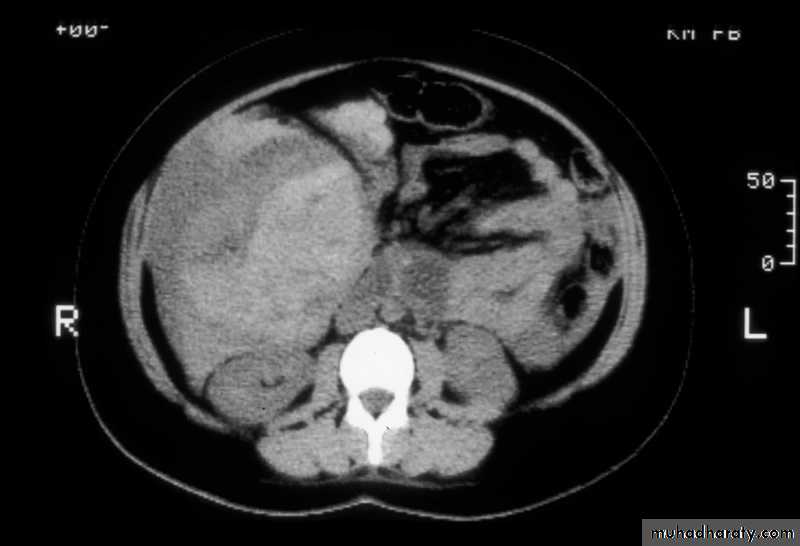

Cirrhosis & portal hypertension

CT

Splenic injurypancreas